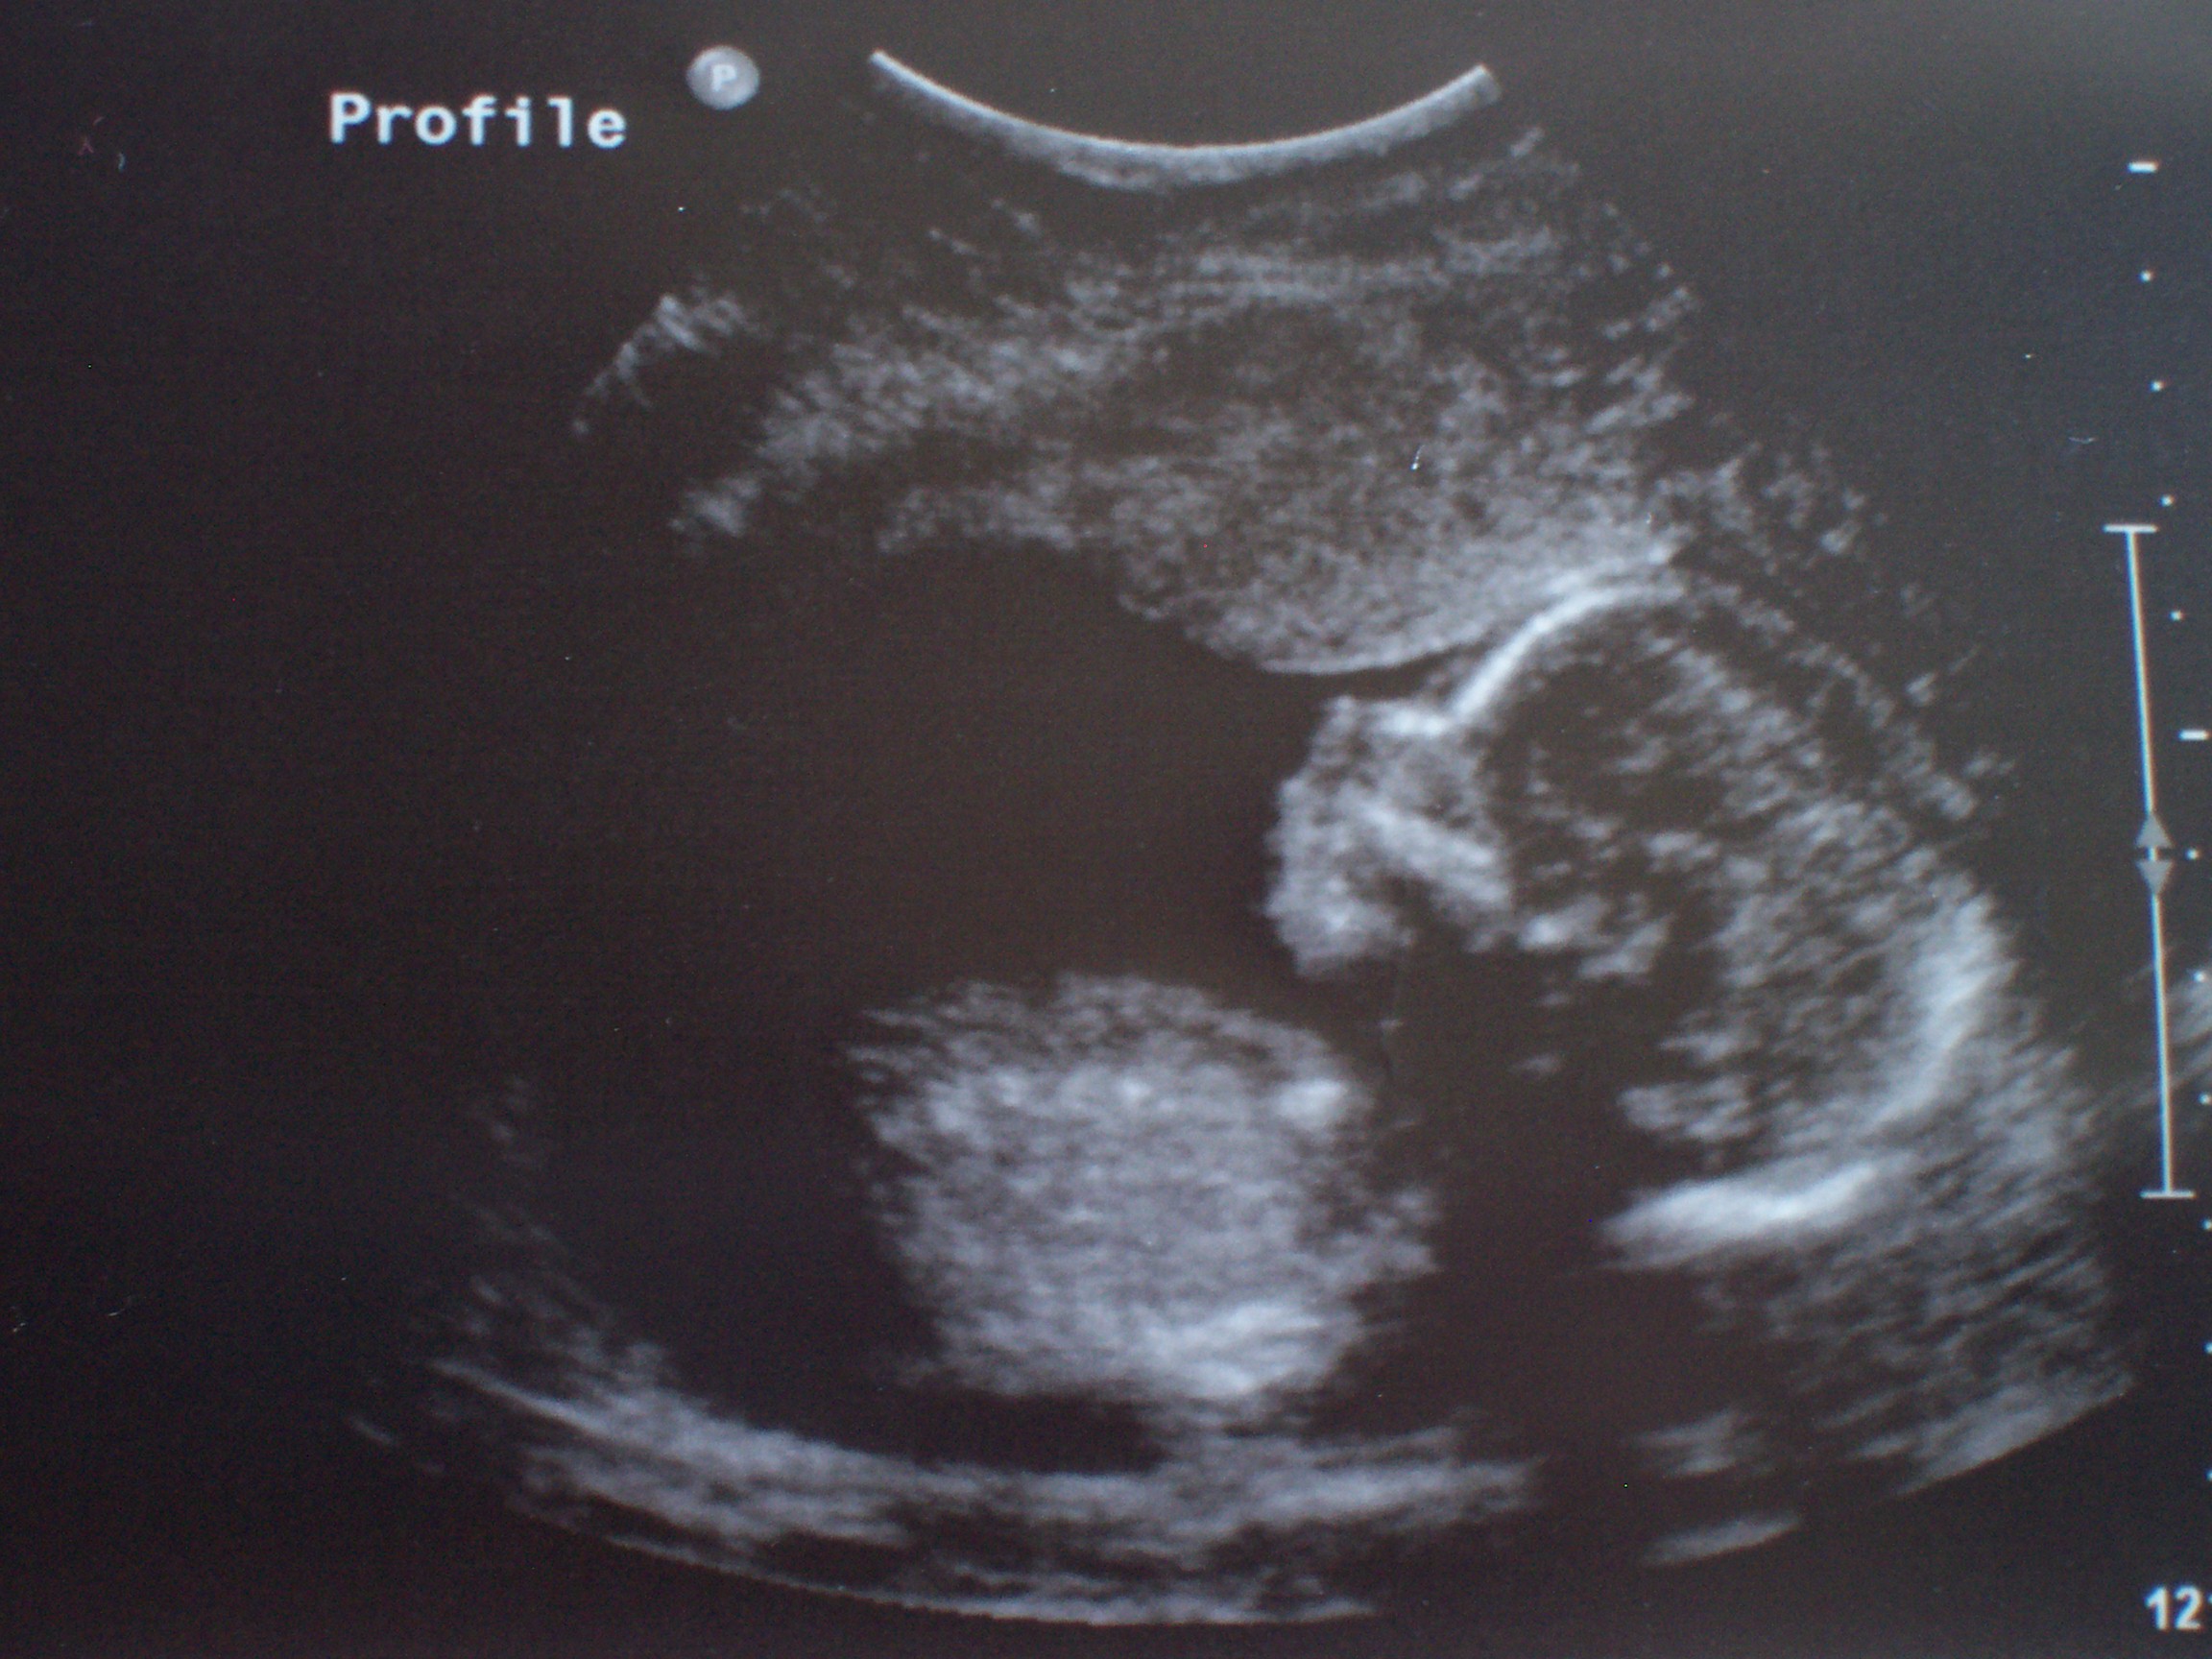

Vincent looks mostly like his dad, except for around his eyes. This baby seems to have my profile, poor dear. You might scoff, but you actually can tell quite a lot from an ultrasound.

The ultrasound went much swifter than I expected — when I was pregnant with Vincent I remember it taking upwards of an hour. Vincent was fascinated and only slightly restless, and what a show the baby put on for us, wriggling around like a fish. Everything looks great and normal, so I’ve opted not to have the amnio.

And the news that (a teeny-tiny percentage of) you have been waiting for: it’s a boy. Unquestionably. And unsurprisingly — this will be Lance’s fourth son — he only makes boys!